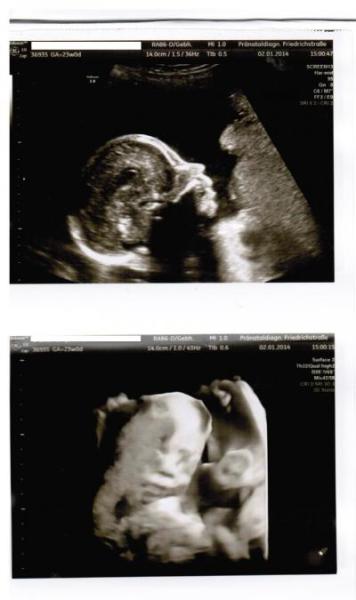

Huhu! Heute hatte ich endlich meinen Termin zur Feindiagnose, nachdem beim zweiten Screening vor zwei Wochen ein Whitespot im Herzen gefunden wurde. Heute konnte dieser aber zum Glück nicht mal mehr gefunden werden Ansonsten war auch alles super und ich habe nochmal sehr deutlich sehen können, dass es wirklich ein Junge wird ;) Ich war total überrascht, wie sehr das Baby aussieht wie unser großer Sohn! Jetzt schon! Super süß! Hab euch auch mal zwei Fotos angehängt. Auf dem zweiten muss man gut hinsehen, aber wenn man sich erstmal zurecht gefunden hat, kann man super schön sein Gesicht erkennen (etwas von meiner VW-Plazenta verdeckt)

Bild zu Bericht FD nach Whitespot-Fund - Forum für Mai - Mamis